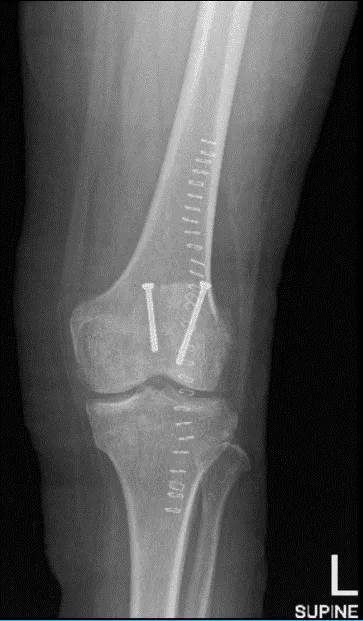

Un paciente de 68 años estaba en nuestra consulta con quejas, las radiografías postoperatorias en la revisión mostraron cortes en los tornillos y fallo en la fijación con desplazamiento de la fractura. El Dr. Karkare habló sobre las opciones de tratamiento y el paciente optó por el manejo quirúrgico en forma de revisión.

Cuando la fractura se redujo bien, se decidió probar un cableado de banda tensión. Se pasaron dos cables guía por media y lateral y se convirtió. Hallazgos en una posición aceptable en la vista AP y lateral y lo suficientemente profundos.

Se realizó el taladro sobre los cables guía y se colocaron tornillos cancellados canulados de 4 mm. Ambos tornillos de 4 mm estaban 6 mm más pequeños por medir los cables guía. Se pasaba una cinta de fibra de 2 mm a través de estos cables guía en una configuración en forma de ocho. Este FiberTape mostró una buena reducción de modo que el FiberWire se ató con un nudo en el aspecto superolateral.

El paciente fue atendido para una visita de seguimiento y presentó resultados de radiografía que mostraron cambios postquirúrgicos sobre la rótula con una posición satisfactoria del hardware. Por lo demás, un examen poco destacable.

Radiografía de rodilla izquierda AP y lateral